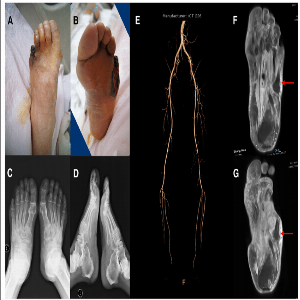

We Provide Best Doctor For Diabetic Foot Problem